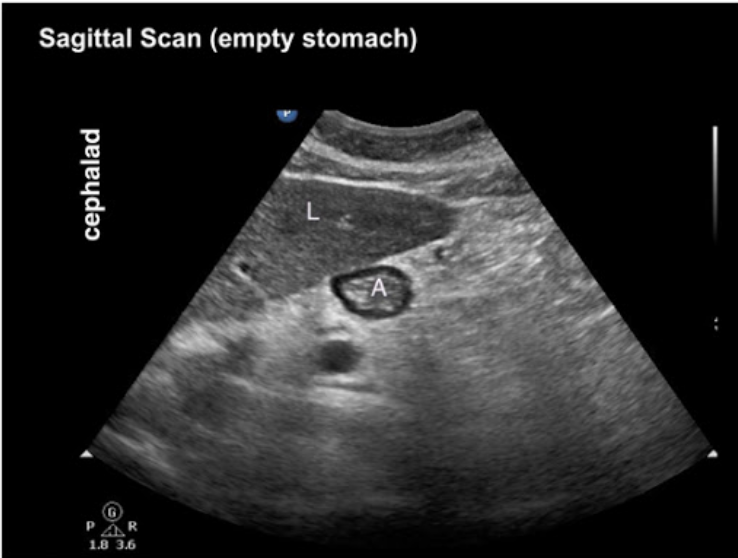

20.1 The structure labelled A shows

A

a. Empty stomach